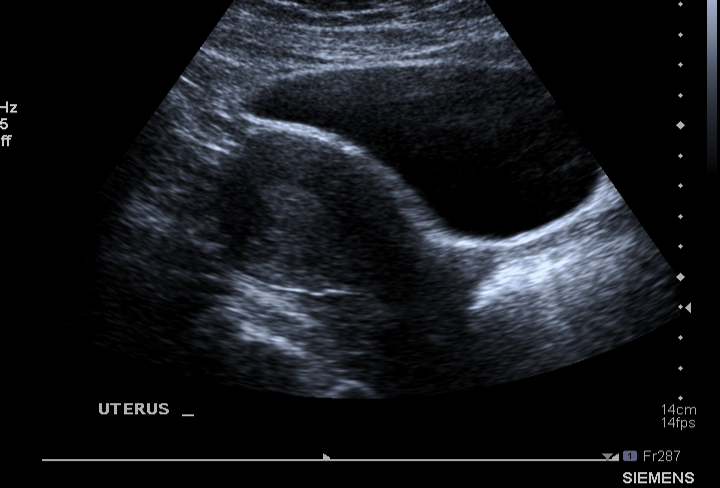

What structure is being shown in this US pic ?